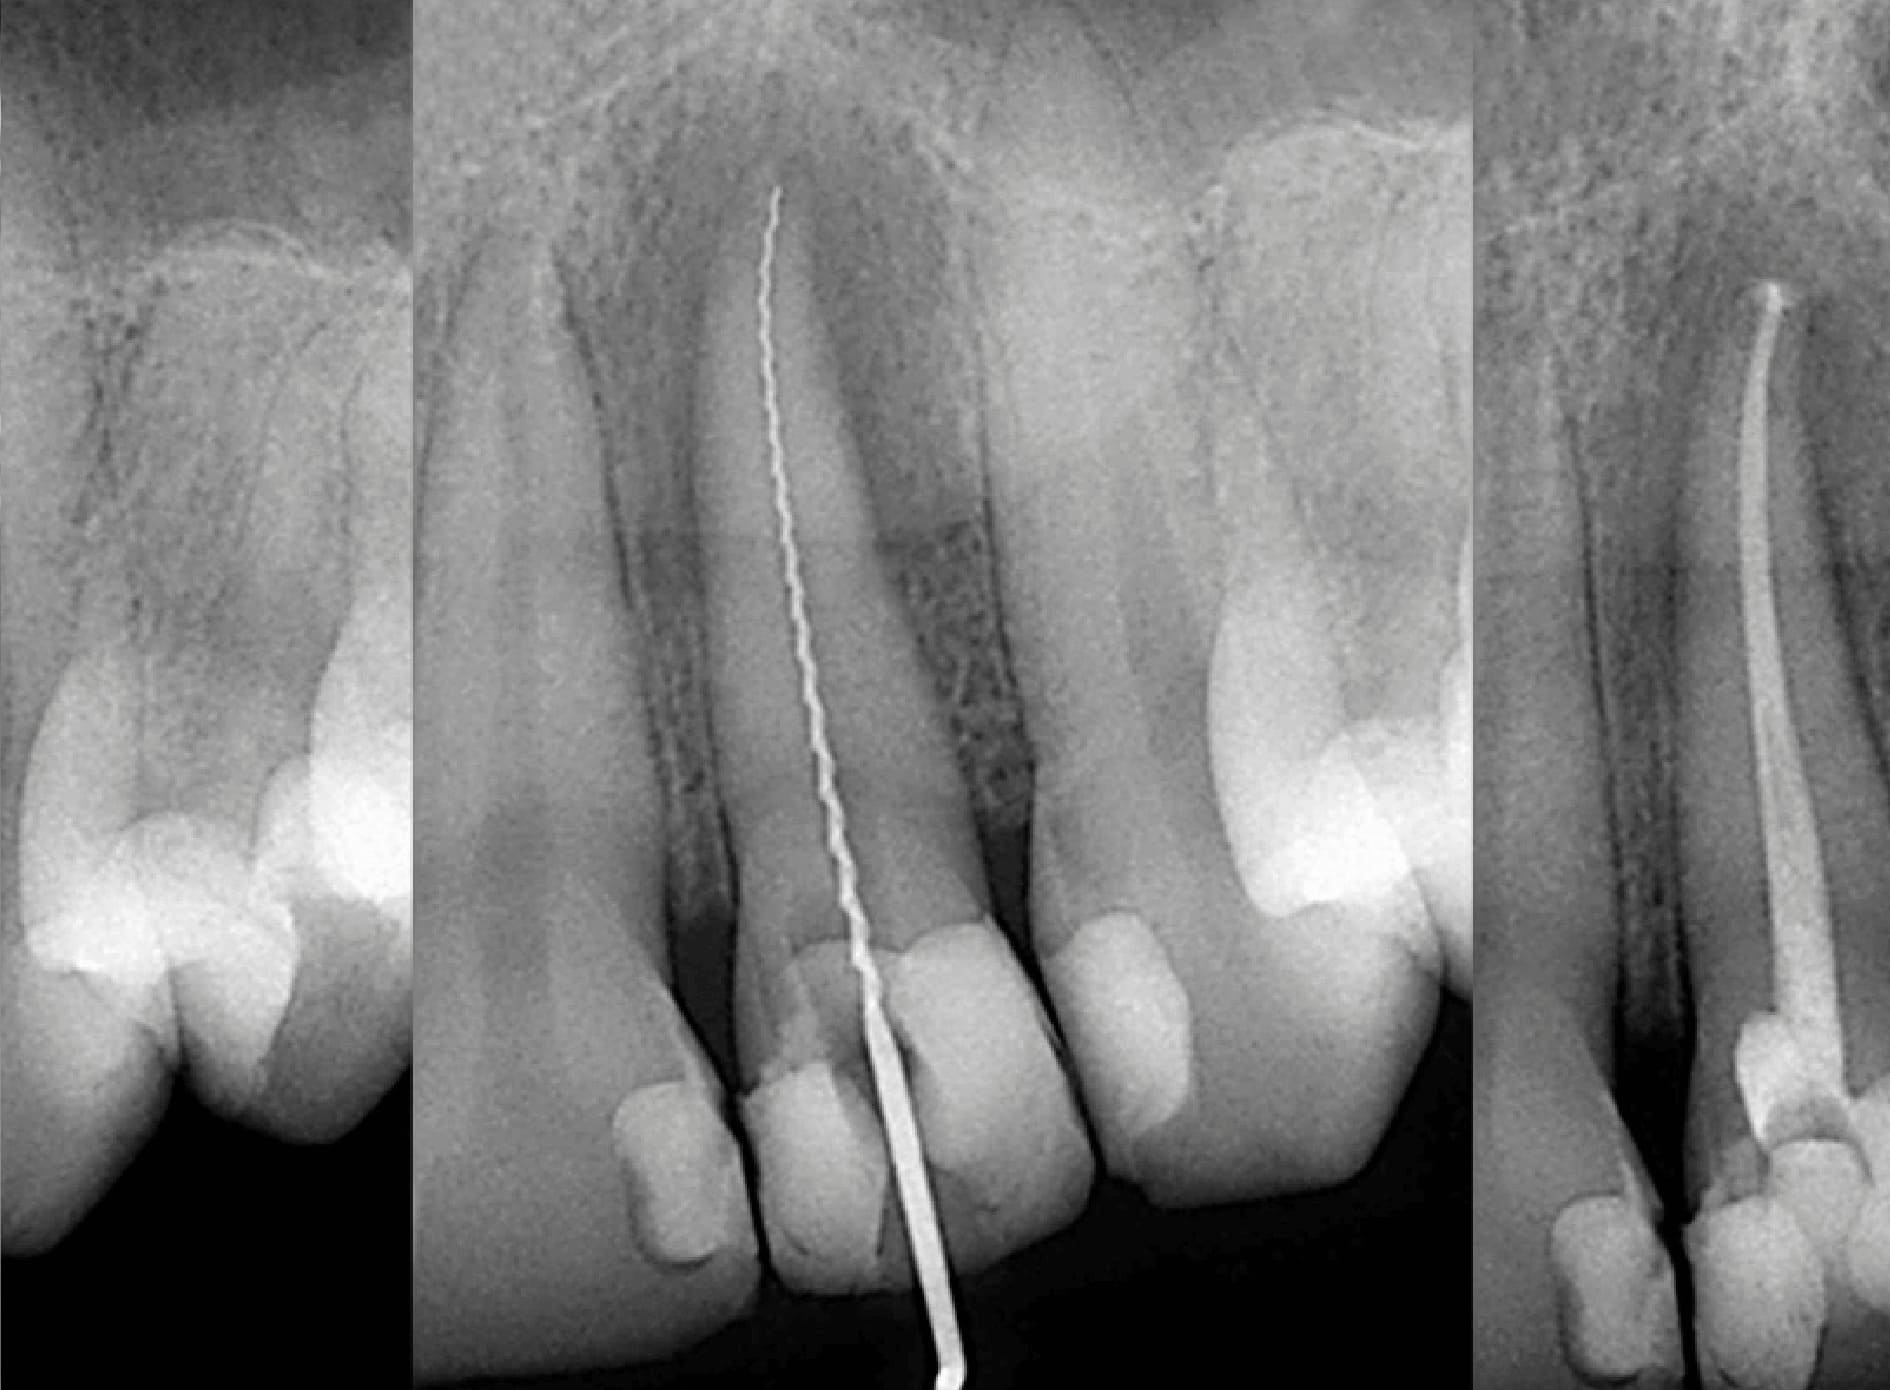

Una endodoncia es un procedimiento de alta precisión para salvar un diente que de otra manera tendría que ser extraído. En GM Dent, usamos tecnología moderna para garantizar un proceso cómodo y seguro.

Tratamiento de Endodoncia